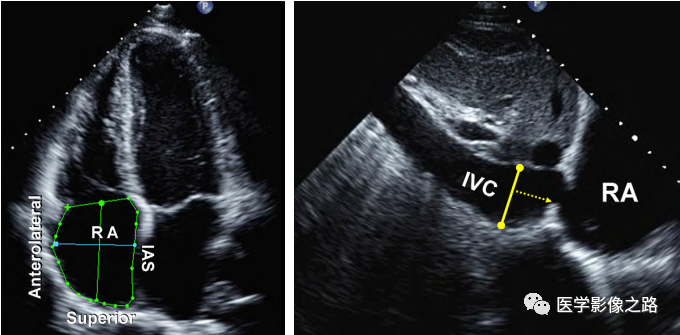

3.右室收缩和舒张功能

什么叫超声容积探头医学超声影像学笔记——心脏正常的解剖和超声评价_https://www.jmylbn.com_新闻资讯_第15张

⑴面积变化率(FAC):四腔心切面,测量右室收缩期和舒张期的面积。FAC=(舒张期面积-收缩期面积)/舒张期面积。FAC>35%正常

什么叫超声容积探头医学超声影像学笔记——心脏正常的解剖和超声评价_https://www.jmylbn.com_新闻资讯_第16张

⑷右心房面积>18mm2,右房上下径>55mm,左右径>44m。提示右房增大

什么叫超声容积探头医学超声影像学笔记——心脏正常的解剖和超声评价_https://www.jmylbn.com_新闻资讯_第17张

IVC<21mm,塌陷率>50% RAP=5mmHg

IVC<21mm,塌陷率<50 OR

IVC>21mm,塌陷率<50% RAP=10mmHg

IVC>21mm,塌陷率<50% RAP=15mmHg